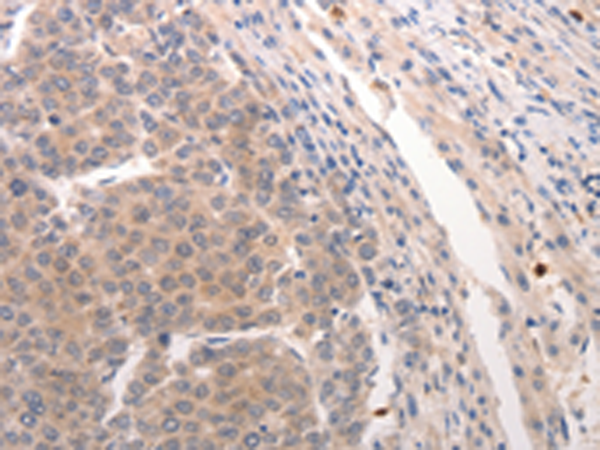

分类: 科研抗体货号: P10725别名: BNP; Iso-ANP应用: IHC反应种属: Human